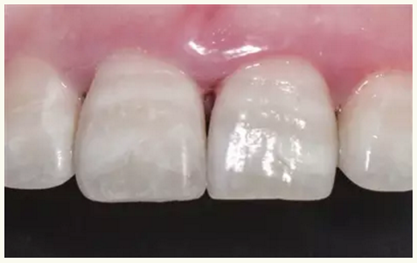

▲術(shù)后一月(唇側(cè))

▲術(shù)后一月(舌側(cè))